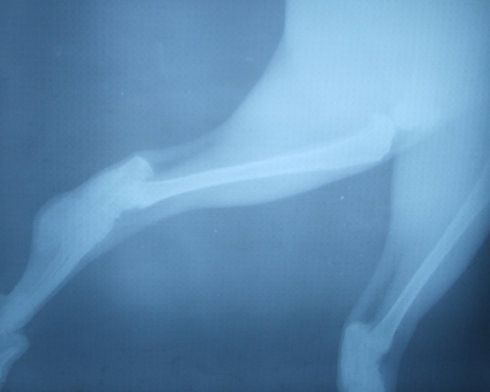

主人提供的照片:

看完邮件后,我觉得这个猫患骨软骨发育不良的可能性非常大。

从现有的材料来看我也不能100%的确定就是这个问题。因为主人提供的X线片质量一般,看得不是很清楚。并且没有提供其它几个肢体的X线片。我建议,应该再拍摄几张高质量片子,特别是看似正常的肢体。没有症状,并不能说明没有病变。

苏格兰折耳猫骨软骨发育不良是一种影响骨生长和关节软骨形成,致使四肢远端和尾部渐进性骨骼畸形的遗传性疾病。最初认为此病仅仅发生于纯种折耳猫,并由常染色体控制。后来有不少人报道与折耳杂交的猫也有类似的发病情况,但是严重程度较轻微。随着病情发展也出现不同症状的骨骼异常,如渐进性跛行、步态僵直、高抬腿、不愿跳跃或走动。由于此病是基因缺陷导致的,因此治疗的目的是减低临床症状和止痛。 此病最初被认为是基因自身突变引起的,在1966年,通过繁殖实验,发现此病是常染色体控制的遗传性疾病。此纯合基因控制着四肢末端及尾部渐进性骨骼病变。在7周龄时放射学改变已经非常明显。